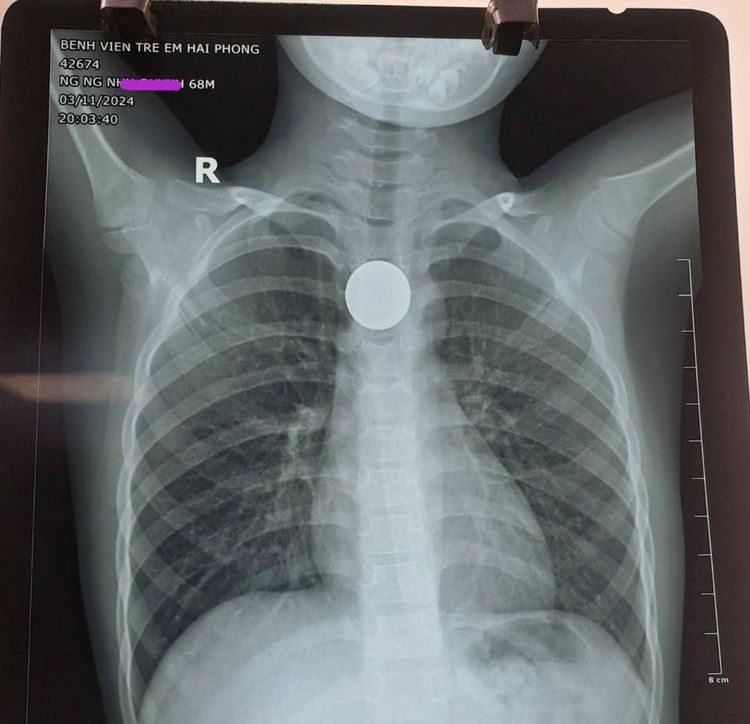

Cháu bé nhanh chóng được tiến hành gây mê, nội soi và gắp kịp thời đồng xu kích thước gần 3cm ra khỏi đoạn 1/3 giữa thực quản an toàn. Sau khi được nội soi gắp thành công đồng xu ra khỏi thực quản, hiện sức khỏe cháu bé đã ổn định.

| Đồng xu được lấy ra khỏi thực quản |